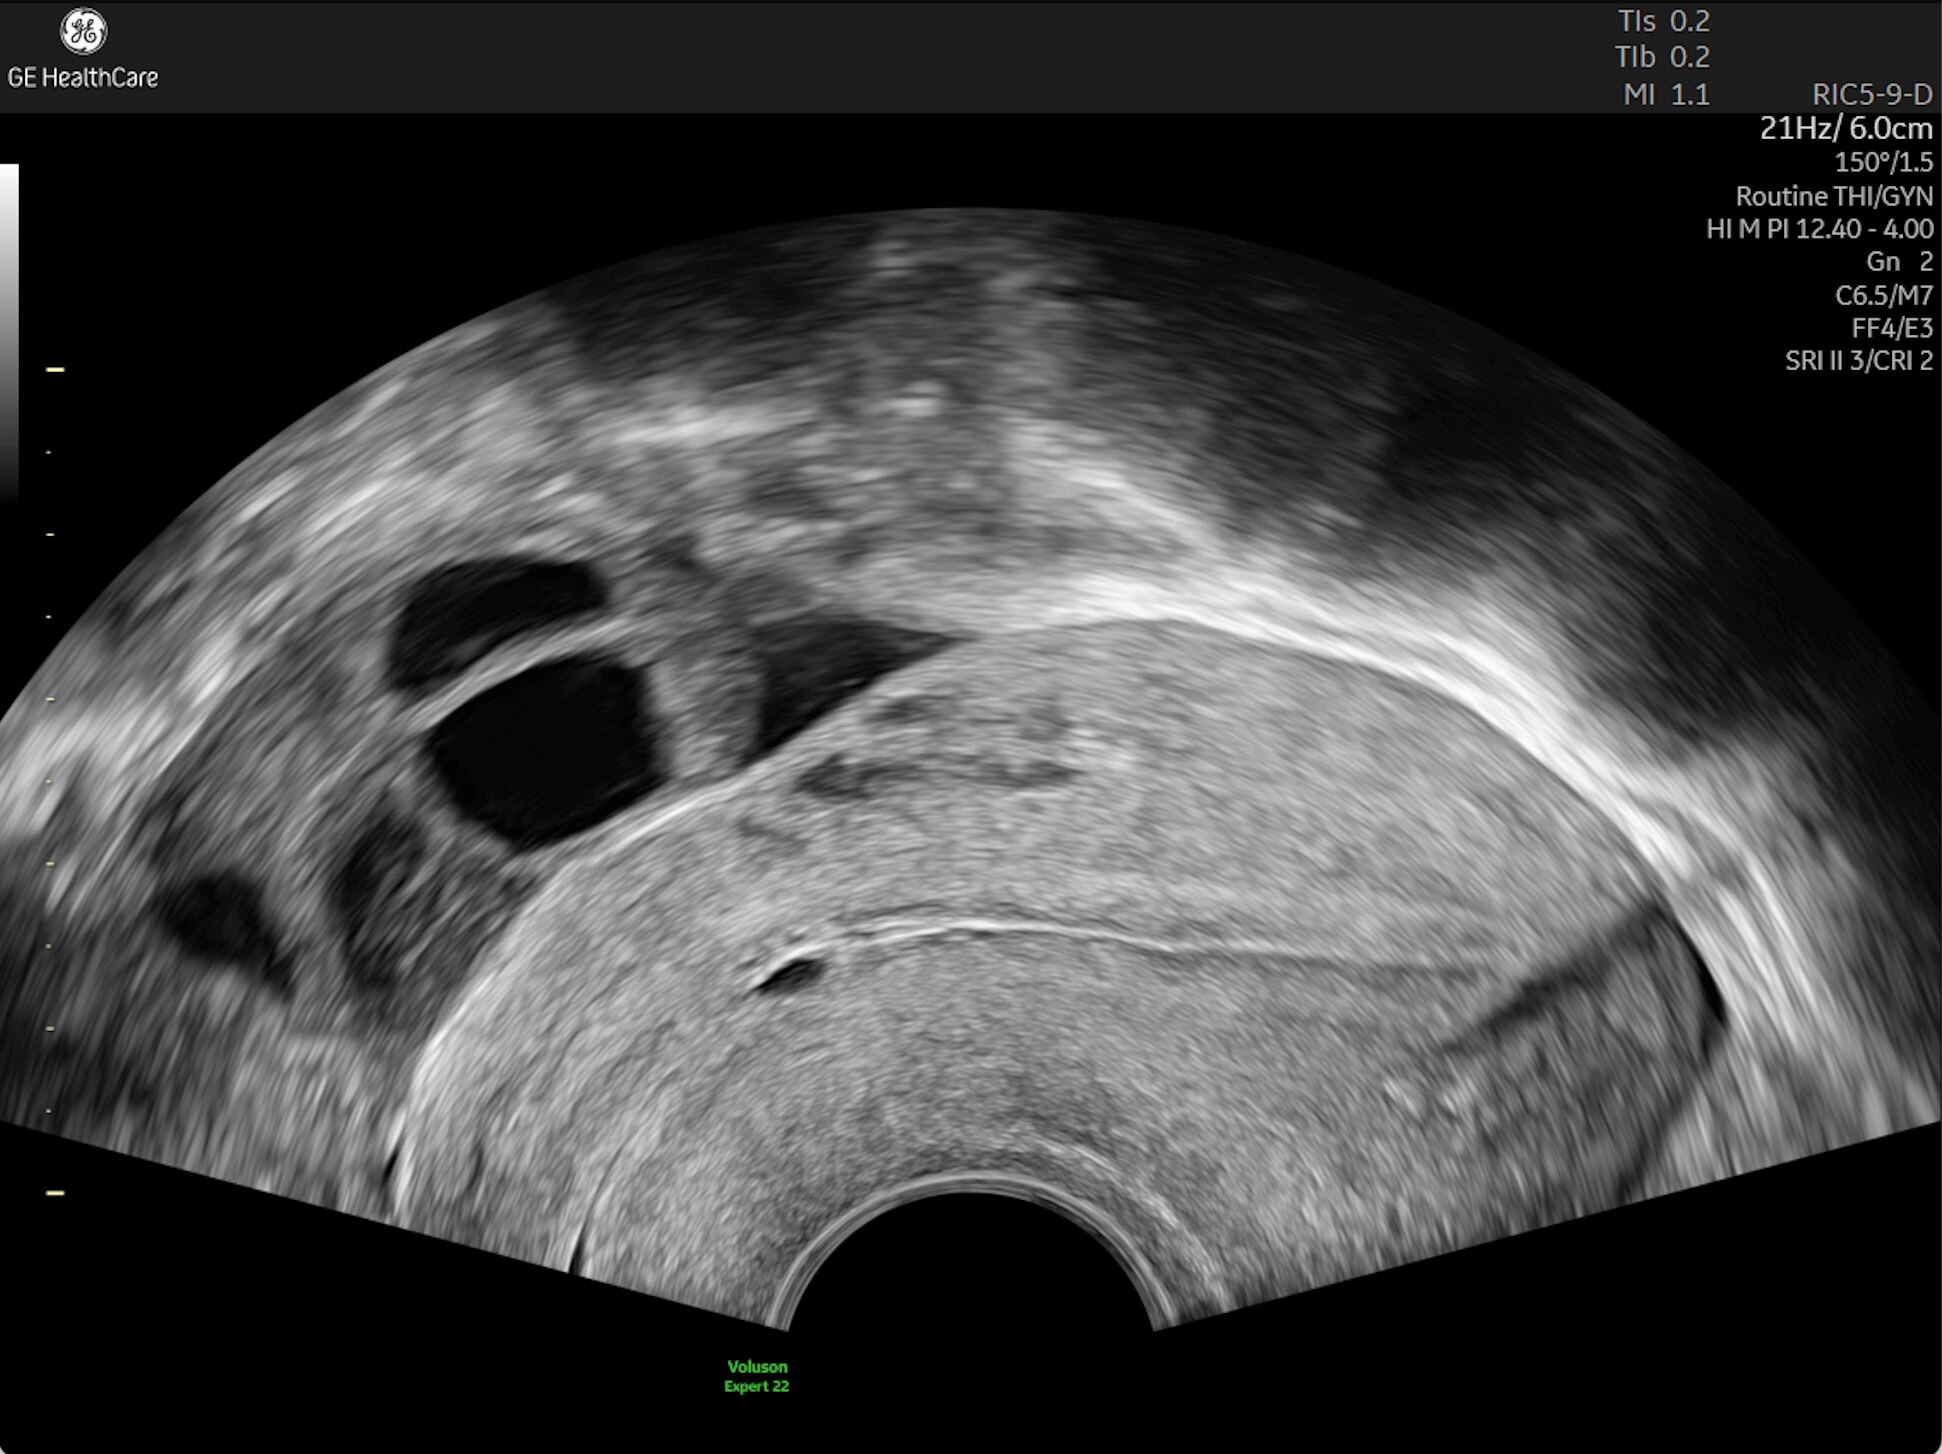

First Trimester Exams

Perform detailed exams with high-resolution for early insights to fetal health